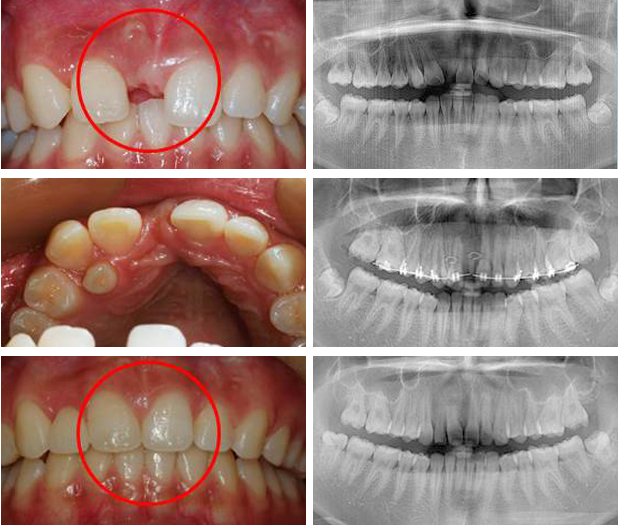

치아교정